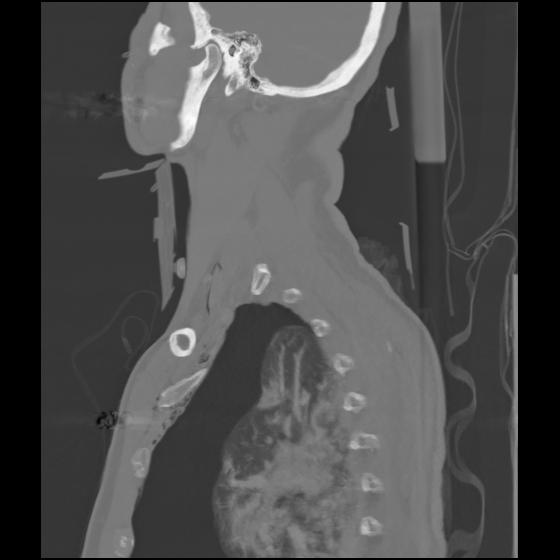

24 ANGIO,CE,Sag-MIP,5.000,ANGIO,Sag-MIP,